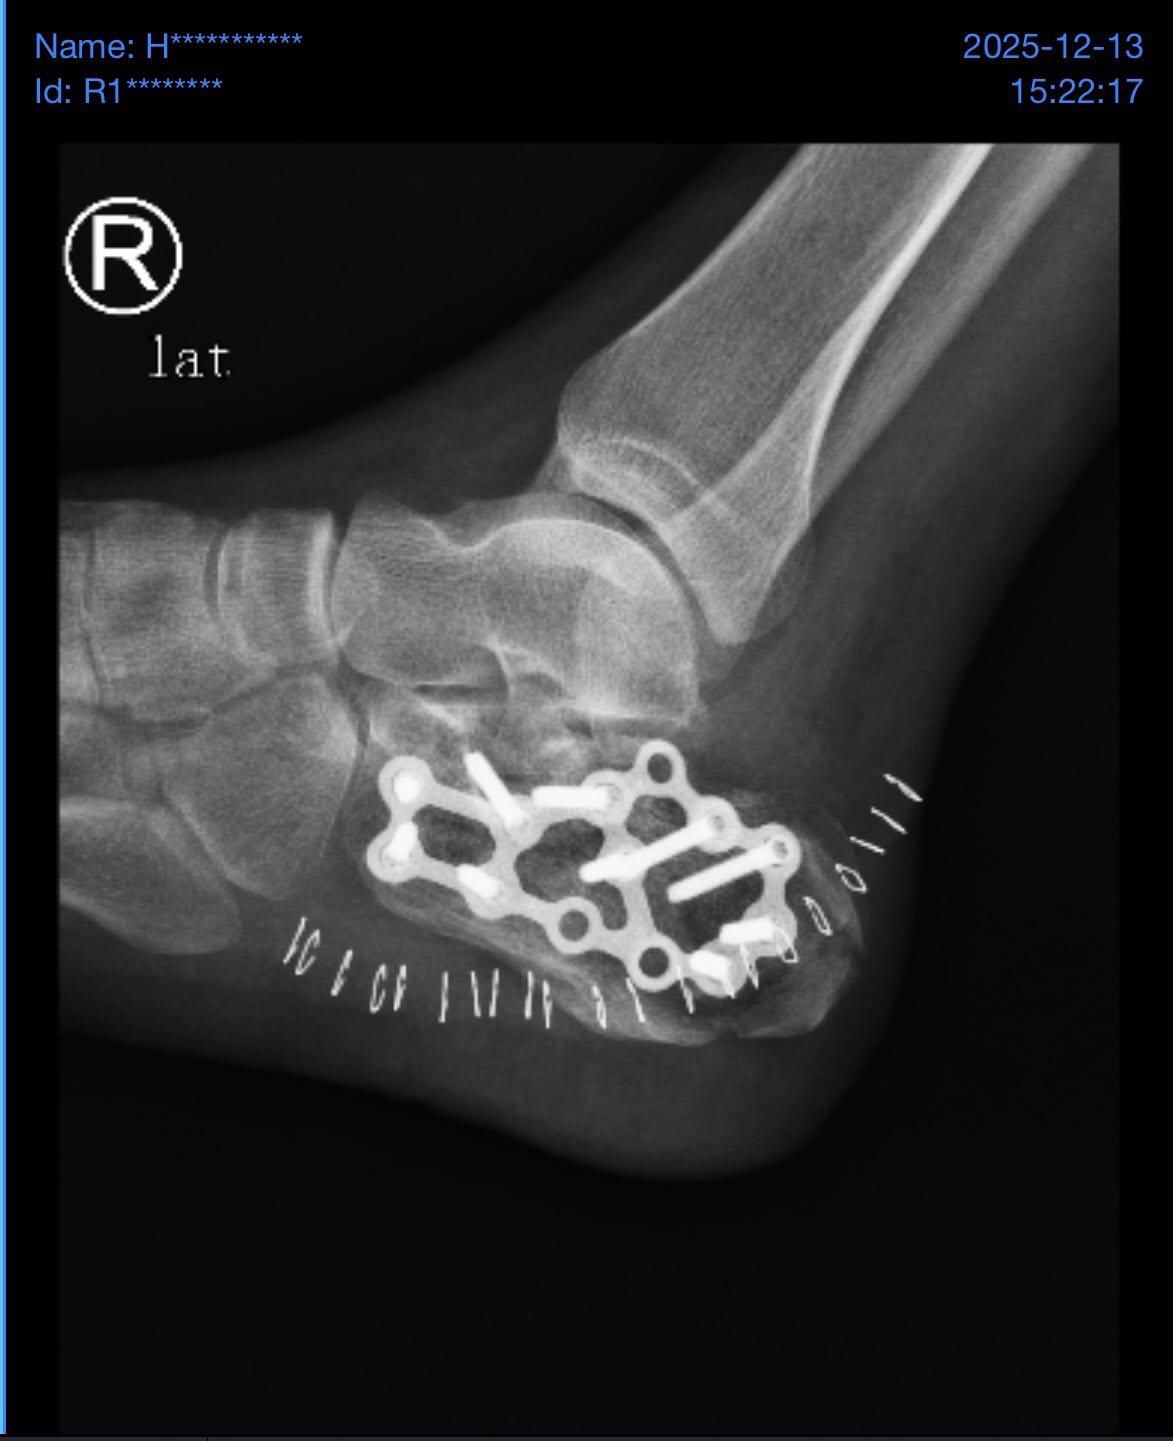

11 月 11 日凌晨 4 点,我从二楼跳下逃跑,当场造成:

- 双脚跟骨骨折

- 左手脱臼

但因无法跑动被抓回园区。

园区老板殴打我,并一脚踩断我的左胫骨,打了10几分钟,随后把我丢在保安室。

我在里面痛了 8–9 小时才被人接出,然后送去医院,一直没交钱,医院就停药了,期间刘*坤怕我从医院跑,还偷偷把我身份证及所有证件哪些拿走,后面找他们要证件回国治疗不同意,自己想办法雇了壹*集团的护卫偷偷把我从医院接出去了,导致20多天没有及时治疗,这个事情不会这么结束的,证据我一大堆,有本事回国!